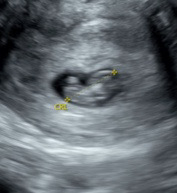

8주에 요정도인데 젤리곰 보려면 다음주에 병원에 또 가야할까요? 2주뒤인 10주에 오라고 하셨는데 그때 가도 젤리곰 볼 수 있을까요!?😀

지금도 거의 젤리곰 형태라서 10주면 보기 어려우실 거예요 명확한 젤리곰을 보고 싶으시면 9주에 가는 게 나을 것 같아요 근데 초음파가 좀 흐릿한데 혹시 질초음파 맞나요?

8주에 젤리곰형태고 10주차엔 사람형태가 생기더라구요 ㅋㅋㅋ